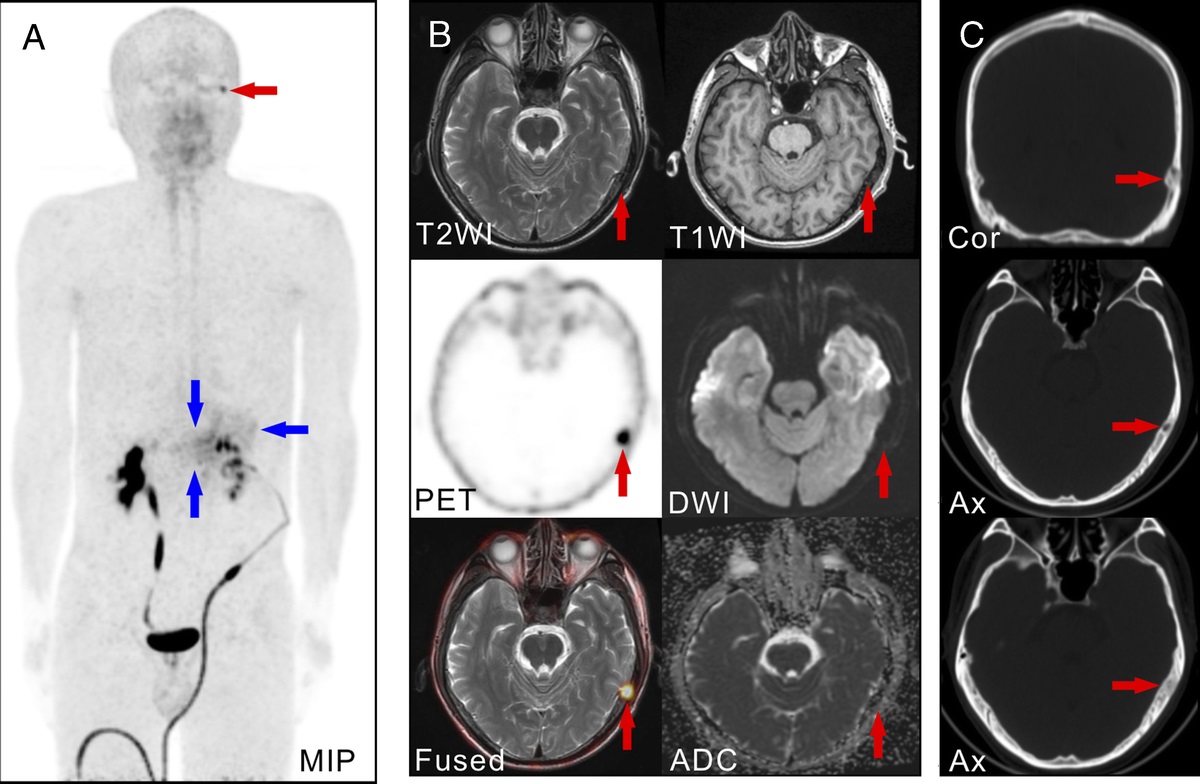

Current Issue: Fibrous Dysplasia Mimicking Skeletal Metastasis on 68Ga-FAPI PET Imaging dlvr.it/STN0Dh

ClinNuclearMed's tweet image. Current Issue: Fibrous Dysplasia Mimicking Skeletal Metastasis on 68Ga-FAPI PET Imaging dlvr.it/STN0Dh